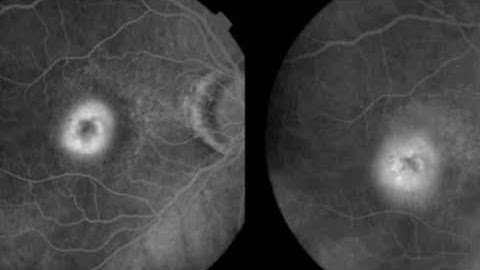

Choroidal neovascular membrane (CNV) | Wet AMD | TYPE 1 CNVM, type 2 CNVM, type 3 CNVM ,RAP